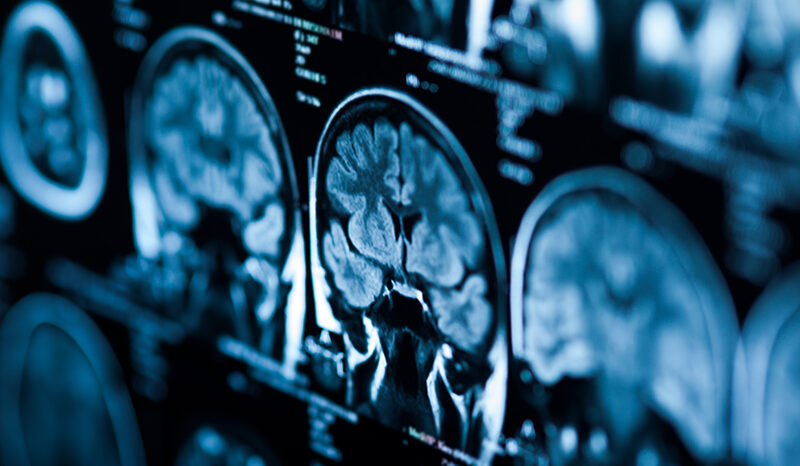

Brain cancer is the abnormal, uncontrolled growth of cells in the brain.

The brain has many different ‘control centres’ that regulate all of our body functions, from breathing to walking. When the cancer grows it can damage these control centres. Even slow growing (benign) tumours can be serious if they affect a vital area of the brain.

The brain is composed of nerve cells that send messages to and from the body, and supporting cells that enable nerve cells to function. Cancer can originate in many different cell types, giving rise to various forms of brain cancer.